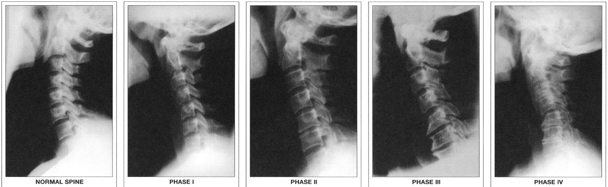

Generally speaking, spinal damage can range anywhere from minor/moderate to severe. To avoid mass hysteria, I’m not suggesting that sleep position will cause severe problems like paralysis… But it can compound minor/moderate irritation and pre-existing spinal misalignments into measurable damage over time. I’m referring to things like hyper-mobile joints, muscle spasm, vertebral disc thinning, postural distortion and other arthritic changes.

It’s tempting and logical to assume that you can feel the effects of spinal decay. While I wish that were true, it’s not always the case. The process can develop very quietly over 10-20 years (or longer) without any urgent symptoms. By the time a person finally decides to seek treatment, it may be too late. This type of decay is irreversible, so it’s important to take care of your spine while you still have options.

Taking care of your teeth is easy because you stare at them every day. But how would you know if your spine is in good shape if you’ve never seen it? I’d estimate that 80% of the American population has never received spinal x-rays. This needs to change so that people can begin making the necessary lifestyle changes – like pillow posture – early enough to make a difference. (Note: If you’re tempted to write me a scathing diatribe for suggesting that your sleep position could be compromising your quality of life, please make sure you’ve actually seen your cervical spine before.)

Keep in mind that it’s much easier to correct spinal problems when you discover them in your 20’s-30’s than it is when a chiropractor points them out to you in your 50’s-60’s.